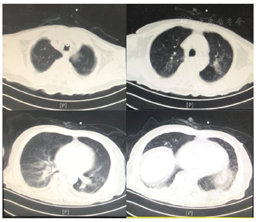

患者医学影像学检查如图1,图2,图3,图4,图5,图6,图7,图8所示,实验室检查结果如图9,图10,图11所示。

2021年3月24日患者出现顽固性低氧血症,血D2-二聚体:12810.00 ng/ml,CTPA显示肺动脉分支栓塞,双下肢静脉彩超:双下肢静脉血栓形成。加用抗凝治疗,调整康复治疗方案:(1)吸氧,监测血氧饱和度下完成康复训练项目;(2)依据患者耐受调整康复训练项目;(3)加强床旁呼吸功能训练。经上述治疗后,患者血氧饱和度有所上升,痰量有所下降,吸痰次数减少。结合患者肺部状况改善的情况给予佩戴说话瓣膜,约4 h/d,同时行语音训练,患者发音逐渐较前稍清晰,痰液可经口咳出,但仍有大量痰液瘀滞于咽部,需要辅助清除,血氧饱和度为85%~95%。2021年5月11日突发寒战、高热、皮肤花斑、咳嗽、大量咳痰,氧饱和度下降至60%。血象、感染相关指标升高;胸部CT:双肺炎症较前加重,双肺间质性病变;支气管三维重建:气管、支气管内分泌物,下叶各段支气管开口显示不清;痰培养:铜绿假单胞菌。经美罗培南抗感染治疗,并加强化痰、气管管理,加强翻身、拍背、排痰宣教后,患者未有发热,咳嗽、咳痰较前好转、感染指标正常;复查支气管三维重建:气道结构通畅;指脉氧饱和度:88%~97%。

高龄85岁患者,因碰撞致摔倒左侧股骨颈骨折,出现跌倒综合征,且早期外院诊疗期间未有康复早期介入出现多种并发症,入住我科后针对患者的肺功能、认知功能、运动功能、吞咽功能等行全面评估及临床症状的全面检查,依据评估结果及影像学实验室检查结果给予全面诊疗。肺部经美罗培南抗感染治疗,并加强化痰、气管管理,加强痰液体位引流、翻身、拍背、排痰宣教、肺功能训练等,患者未有发热,咳嗽、咳痰较前好转、感染指标正常;复查支气管三维重建:气道结构通畅;指脉氧饱和度:88%~97%。经综合临床及康复治疗后患者肺部感染控制,可耐受封堵气管套管4 h,无明显气管症状;可完成床上翻身,部分辅助下卧坐转移;坐位平衡能力达3级;看护下助行架辅助下完成室内短距离步行。